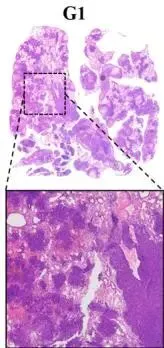

论文Figure 6展示了包封工程细胞在4T1肺转移模型中的治疗效果。实验设计了6个治疗组:G1(PBS对照)、G2(天然细胞)、G3(包封工程细胞暗处理)、G4(包封工程细胞持续表达)、G5(工程细胞红光/远红光调控)、G6(包封工程细胞红光/远红光调控)。

Figure 6B-C的生物发光成像动态监测显示,第1天各组肿瘤负荷基本一致,随着时间推移(第3、7、11、15天),G6组(包封工程细胞RL/FRL)的肿瘤生长抑制效果最为显著,荧光强度增长最缓慢。

第15天的终点分析(Figure 6D)揭示了组间差异。G4组(持续表达)虽有抗肿瘤活性,但血液学分析(Figure 6E-F)显示该组出现白细胞增多(WBC约12×10³/μl)和血小板减少(PLT约400×10³/μl),提示免疫过度激活和潜在的细胞因子风暴相关毒性。相比之下,G6组在实现强效肿瘤抑制的同时,白细胞和血小板计数保持正常范围,证明光控动态调节有效缓解了细胞因子风暴风险。

组织学和免疫荧光分析(Figure 7I-J)提供了直观的治疗效果证据。H&E染色显示,PBS对照组肺组织布满密集的转移结节,而G6组肺部几乎完全清除了转移灶。CD80(抗原呈递细胞标记)和CD8(细胞毒性T细胞标记)的免疫荧光染色显示,活性治疗组(G4、G5、G6)的CD80⁺和CD8⁺细胞浸润显著高于对照组。